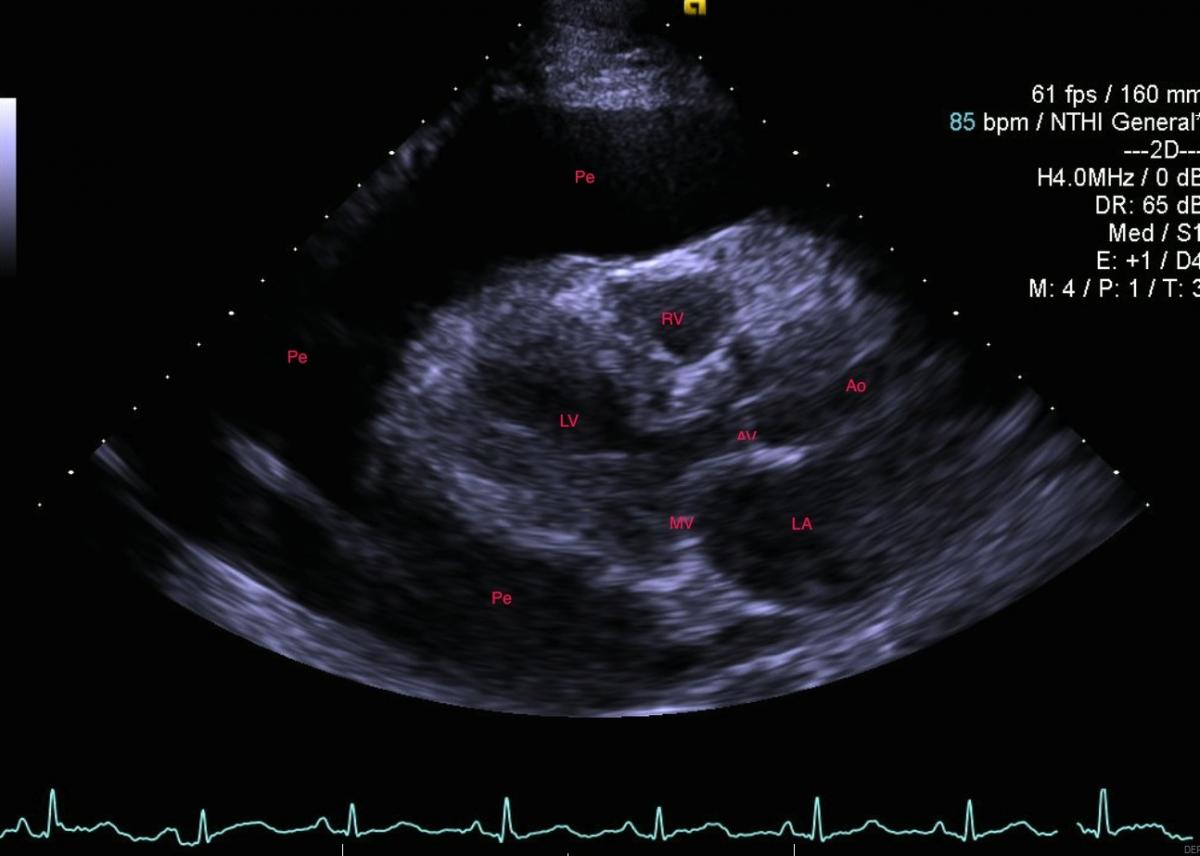

A 58-year-old woman presented with a symptomatic, massive pericardial effusion. Due to shortness of breath for over three months, she underwent percutaneous pericardial drainage (Fig. 1). She had no other significant medical problems.

1.5 liters of serous, odorless fluid was removed and the echo appearance normalized, showing only trace pericardial fluid and a well-preserved ejection fraction. However, within four weeks the effusion re-accumulated as shown in the CXR (Fig.2) and echo showed early tamponade.